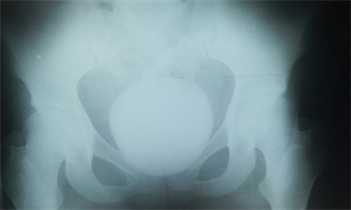

The review by urologist one week post-CS revealed a well preserved lady with healed midline suprapubic scar. There was a bi-manually palpable hard, regular and mobile bladder mass that extends 6 cm above pubic symphysis. Her abdominopelvic ultrasound scan revealed giant vesical calculi with grade 2 to 3 obstructive uropathy. X ray of the region of Kidney, ureter and bladder (KUB) confirmed huge bladder calculus no other stone seen (Figure 1). Urine M/C/S yielded E. coli sensitive to Ciprofloxacin with numerous red blood and pus cells; other laboratory investigations were normal. She was treated for UTI and 2 weeks post-CS had opened cystolithotomy. Intraoperative findings were that of huge bladder stone (Figure 2) weighing 536 g (Figure 3). The bladder wall was thickened with hyperemic mucosa (Figure 4). There was an adequate bladder neck. The histology of the bladder mucosal biopsies showed features of chronic inflammation with Schistosomal ova. Her post-operative care was uneventful; except for a transient frequency on the removal of the catheter that regressed at follow-up.

Figure 1. Plain abdominal X ray (KUB) showing huge bladder calculus no other stone seen.